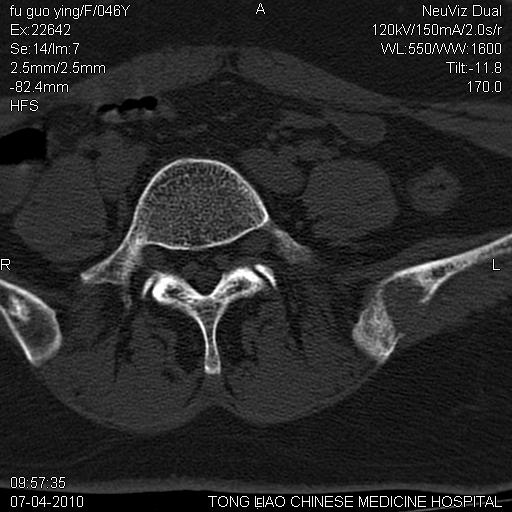

标题: CT27489:患者腰疼,其余椎体未见异常! [打印本页]

标题: CT27489:患者腰疼,其余椎体未见异常!

髂骨考虑转移瘤 椎体病变不像转移瘤

女性46岁,左髂骨溶骨性破坏+软组织肿块,考虑转移瘤,腰椎为退变/增生硬化/软骨下骨囊变。

骨转?骨髓瘤?

骨转?骨髓瘤